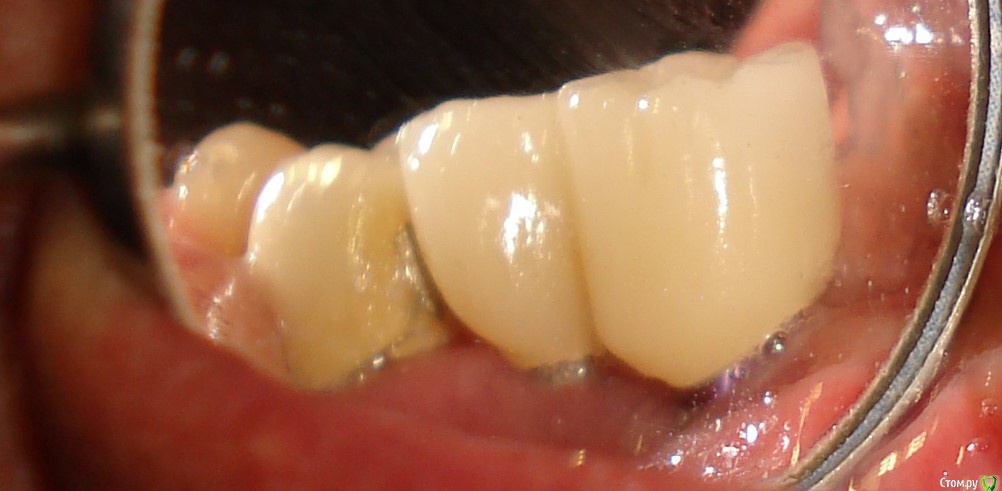

Antikwar Опубликовано 26 ноября, 2017 Поделиться Опубликовано 26 ноября, 2017 Доброго времени суток .Хотелось бы узнать компетентное мнение, врачей, З.техников. Вчера было установленно 2 моста (оксид циркония) на имплантанты перед низ и 2 коронки с боку правая сторона низ ..НА мой не опытный взгляд конструкция и сама работа не качественная и эстетика здесь полностью отсутствует. 1.Видно тело абатмента в обоих конструкциях. 2.Мост и коронки висят в воздухе и не прилегают к десне,как в первом так и во втором случае. Между десной и мостом (перед низ) проходит спичка. Вопрос, должен ли мой доктор переделать эту (на мой взгляд) не качественную работу ! Что вы мне посоветуете .... Заранее благодарю всех откликнувшихся. Ссылка на комментарий

chervoncevdaniil Опубликовано 26 ноября, 2017 Поделиться Опубликовано 26 ноября, 2017 Доброго времени суток .Хотелось бы узнать компетентное мнение, врачей, З.техников. Вчера было установленно 2 моста (оксид циркония) на имплантанты перед низ и 2 коронки с боку правая сторона низ ..НА мой не опытный взгляд конструкция и сама работа не качественная и эстетика здесь полностью отсутствует. 1.Видно тело абатмента в обоих конструкциях. 2.Мост и коронки висят в воздухе и не прилегают к десне,как в первом так и во втором случае. Между десной и мостом (перед низ) проходит спичка. Вопрос, должен ли мой доктор переделать эту (на мой взгляд) не качественную работу ! Что вы мне посоветуете .... Заранее благодарю всех откликнувшихся.СУдя по фото у вас убыль костной и мягких тканей в области ипмлантов.А состояние соседних коронок на зубах вас не смущают? Ссылка на комментарий

krokomot Опубликовано 27 ноября, 2017 Поделиться Опубликовано 27 ноября, 2017 целевая зона на снимке замылена, четкости нет, исходя из ваших фотографий проблемма не в коронках, а в позиции имплантатов - видна шейка имплантата, так быть не должно. нужны прицельные снимки этой области. Учитывая обстоятельства коронки изготовливаются исходя из положения имплантатов.и я так понимаю вас запротезировали из позиции то что есть, и вая явно нужно что-то делать. Ссылка на комментарий